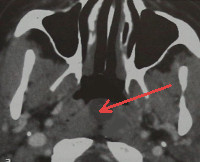

• Лучевые методы диагностики. Результаты КТ и МРТ носоглотки отображают наличие круглого полостного образования размером от 0,5 до 4,5 см с четкими контурами и гладкой внутренней поверхностью, расположенного по срединной линии глотки. У некоторых больных эта структура может иметь дренирующее отверстие.